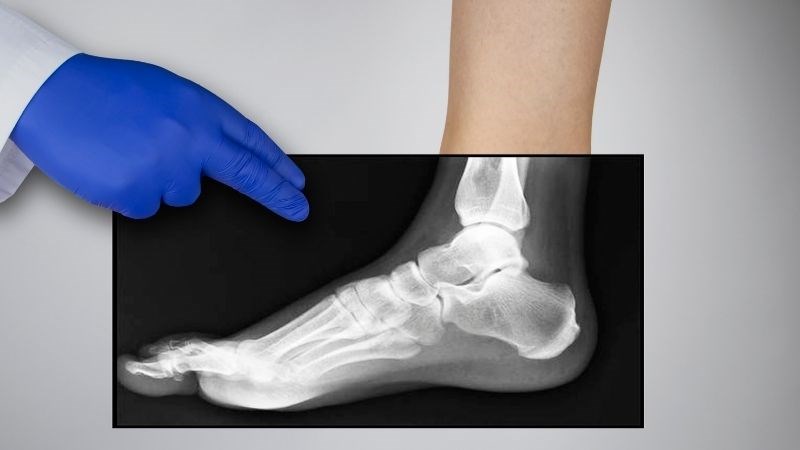

Chụp X-Quang

X-quang là xét nghiệm sử dụng năng lượng của tia X để thu được hình ảnh về các xương ở bàn ngón chân. Bác sĩ sẽ dựa vào những hình ảnh này để đánh giá tình trạng mất sụn hay thay đổi hình dạng của các khớp xương.

Để xét nghiệm này đạt hiệu quả, bác sĩ sẽ yêu cầu người bệnh đứng thẳng.

Chụp X-quang là xét nghiệm được sử dụng nhiều để đánh giá tình trạng khớp ngón chân